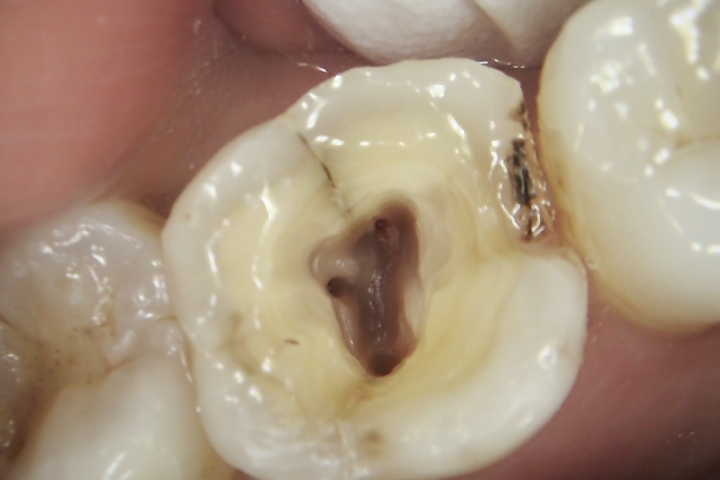

治療前後の写真を確認していただきますので、どれだけ大きな虫歯が隠れていたのか、痛みのリスクがどれぐらいあるのか等、イメージがしやすいと思います。

治療前と治療後の写真を比較することができます。

保存学会認定医による、根管口を口腔内カメラで画像管理しながらの根管治療を行います。